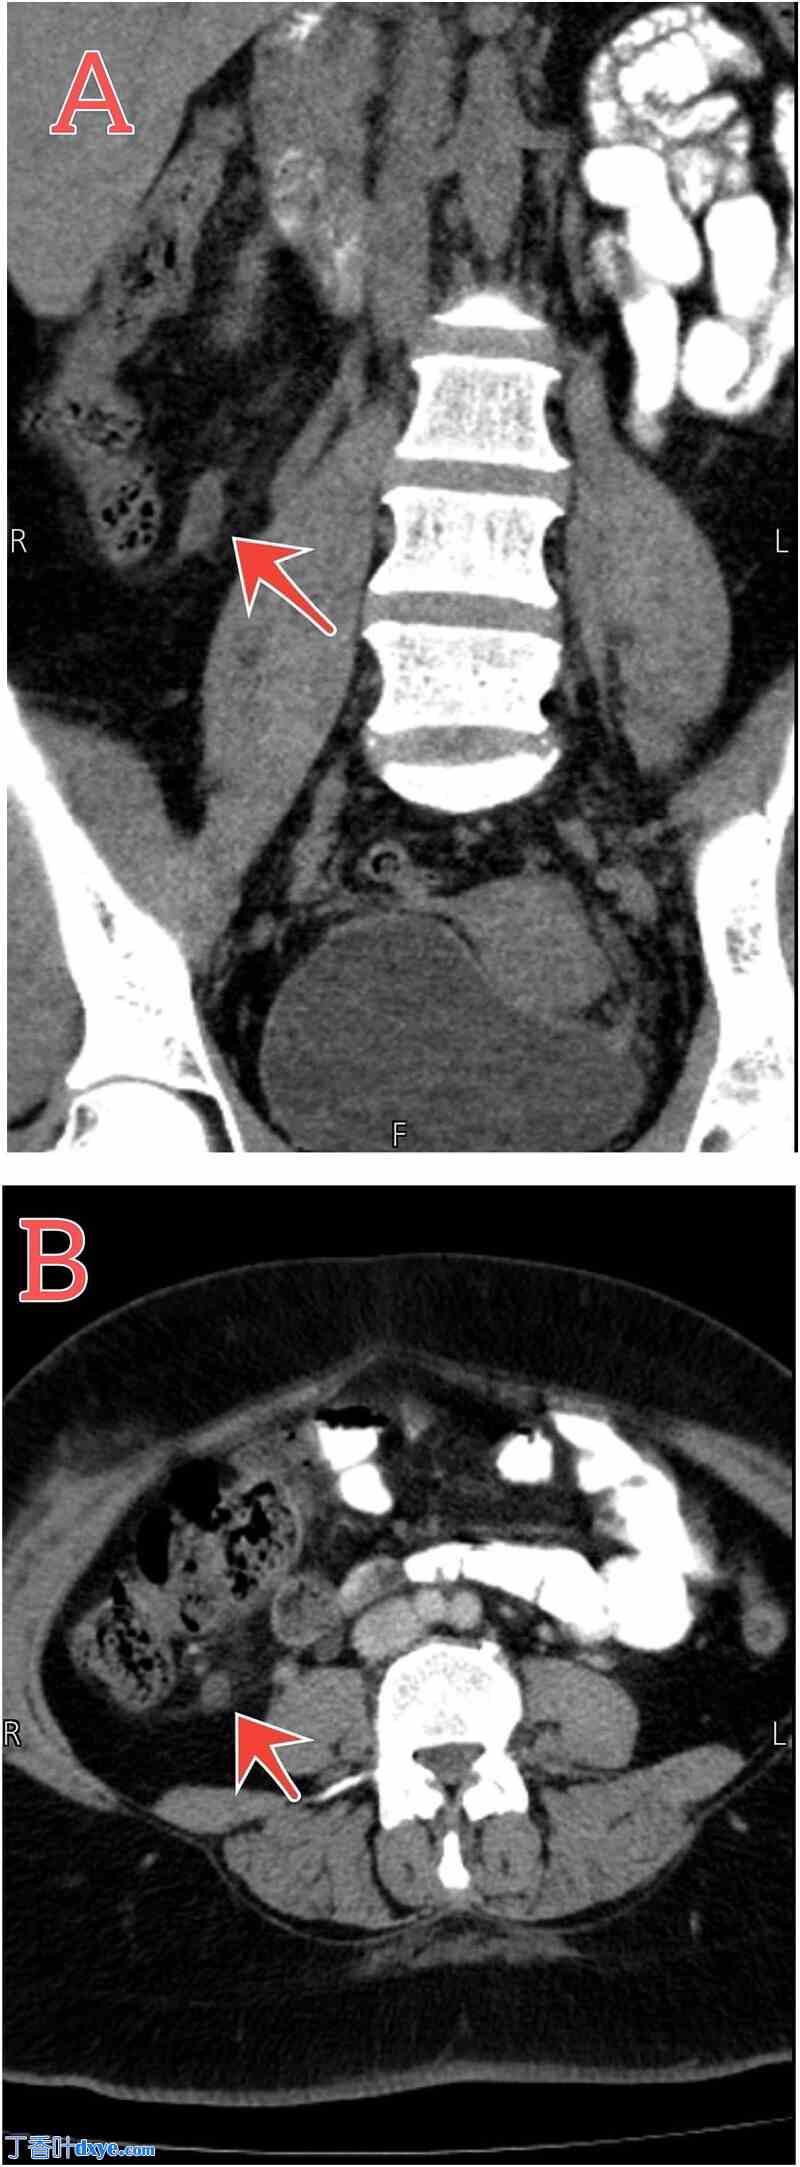

进一步检查以确诊,全血细胞计数显示白细胞升高,伴有左移,C反应蛋白 (CRP) 阳性,为16 g/L。妇科会诊排除任何妇科病因,超声检查结果正常。尿液分析结果正常。为此,患者既往有阑尾切除术病史,随后进行了腹部和盆腔增强CT扫描。CT结果显示残留阑尾远端炎症,伴有黏膜强化和周围轻度脂肪条带,证实了复发性阑尾炎的诊断(图1)。

腹部盆腔CT扫描显示阑尾炎。(A和B)冠状面和轴向切面显示盲端管状结构的远端部分,该结构长约8毫米,起源于盲肠(红色箭头),伴有黏膜强化和周围轻度脂肪条带。